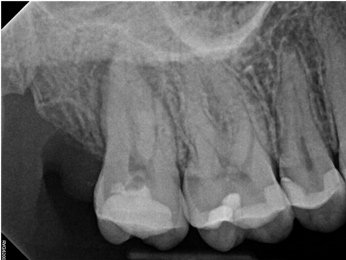

In the first case study, a young female patient was told she had a tooth (tooth No. 2, Figure 3) that should be extracted due to extensive bone loss. Using CBCT, the clinician was able to identify a large lateral canal within the palatal root. Despite the bone loss, the patient was eager to save her tooth. He offered to treat the tooth with the broad-spectrum acoustic technology. As shown in Figure 4, the preparation space was much smaller, which he was able to obturate efficiently. In addition, the small pinpoint of sealer in the middle of the palatal root indicated that the palatal lateral canal had been addressed (Figure 5). In the clinician's opinion, this area was likely the primary source of much of the bone loss.

Fig 3. Case 1: CBCT showed a large lateral canal within the palatal root (Fig 3). There was a small preparation space, which was efficiently obturated (Fig 4). A small pinpoint of sealer in the middle of the palatal root indicated that the palatal lateral canal had been addressed (Fig 5). After 5 months, CBCT demonstrated complete healing (Fig 6), notably on the distal, where probing had resolved to 2 mm. Radiographic images were taken immediately postoperatively (Fig 7) and 5 months postoperatively (Fig 8).

Figure 3

Fig 4. Case 1: CBCT showed a large lateral canal within the palatal root (Fig 3). There was a small preparation space, which was efficiently obturated (Fig 4). A small pinpoint of sealer in the middle of the palatal root indicated that the palatal lateral canal had been addressed (Fig 5). After 5 months, CBCT demonstrated complete healing (Fig 6), notably on the distal, where probing had resolved to 2 mm. Radiographic images were taken immediately postoperatively (Fig 7) and 5 months postoperatively (Fig 8).

Figure 4